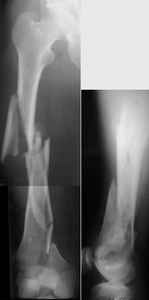

THX, initial images are

1,

2.

At that moment we had in stock only the 10 mm solid nails so of course there was no idea about early weight bearing. But it was quite enough for early knee ROM excersises (see attached). Two locking screws through the distal block provided that.